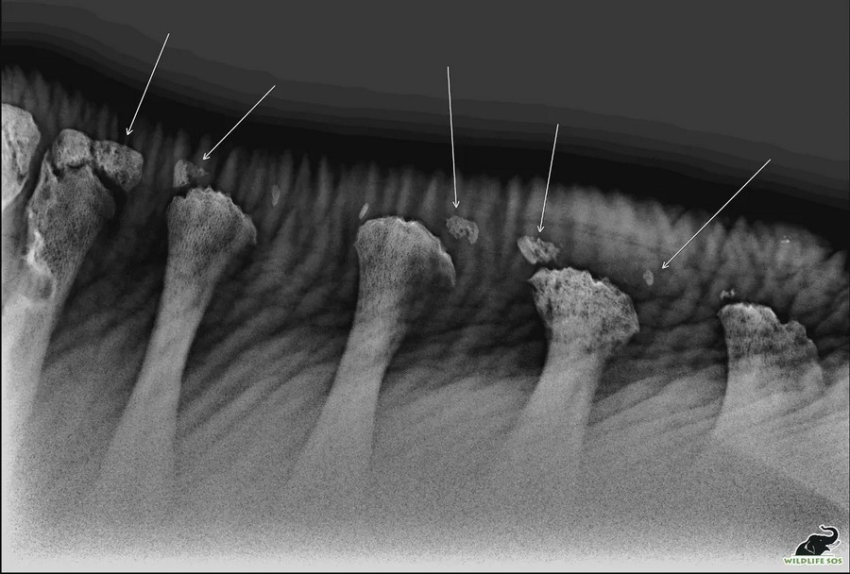

Слон, якому приблизно 25 років, був вкрай виснажений, з випираючими кістками та з численними пораненнями, коли його знайшли співробітники Wildlife SOS. Ветеринари були шоковані масштабами цих травм. Вони виявили, що його хребет поцяткований переломами, а остисті відростки зламані вздовж спини. Вони вважають, що причиною цього, швидше за все, стало неправильне сідло і перенесення важких вантажів, наприклад, груп туристів.

Рентгенівський знімок показує численні переломи й фрагментації на спинному відділі хребта Рами. (Courtesy of Wildlife SOS)

Ветеринар робить рентгенівський знімок хребта Рами. (Courtesy of Wildlife SOS)